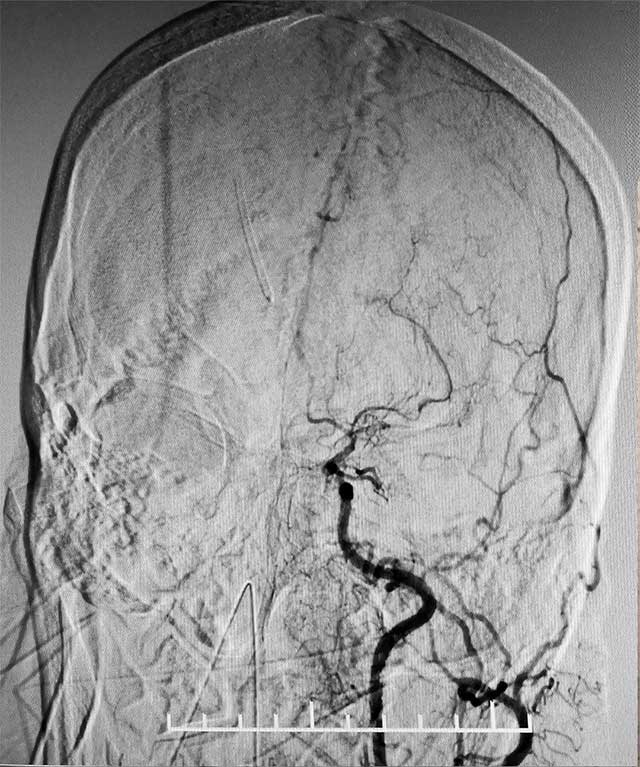

▲ 术前造影显示,患者双侧颈内动脉末端闭塞,颅内烟雾状血管形成

经脑血管CTA和DSA检查,结果显示,患者双侧颈内动脉末端闭塞,左侧大脑中动脉闭塞,颅内烟雾状血管形成,左侧颞顶枕叶灌注不足明显,颅底出现细如烟雾的代偿血管网络,脑部供血严重不足。结合病史,患者部被确诊为烟雾病,由于代偿血管壁长期受到异常血流冲击,形成动脉瘤导致脑出血。张琪博士决定为其实施复合手术室下颅内外血管搭桥联合硬脑膜翻手术。由于患者脑血流非常薄弱,任何风吹草动,都有可能出现脑梗、脑出血。另外,在手术过程中,在全身麻醉状态下,可能出现血压降低,造成脑梗。所有这些无疑增加了手术难度和风险。